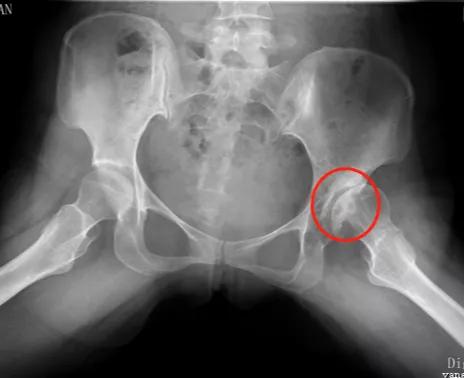

刘万军主任在听取了杨女士的病情描述后,细心安排其做了各项检查,经过检查,左髋臼发育浅,股骨头变扁,密度不均匀,关节面毛糙,关节间隙狭窄,髋臼上缘边缘硬化,关节半脱位。 诊断为:左髋关节发育不良,轻度扁平髋,继发骨性关节炎,关节半脱位。

对于刚出生的婴幼儿,可通过超声检查筛查髋关节发育不良,而对于成人髋关节发育不良患者来说,临床上最常用的为X线检查,主要表现为髋臼发育浅小,股骨头的负重侧间隙变窄等,必要时进行 CT和MRI检查。